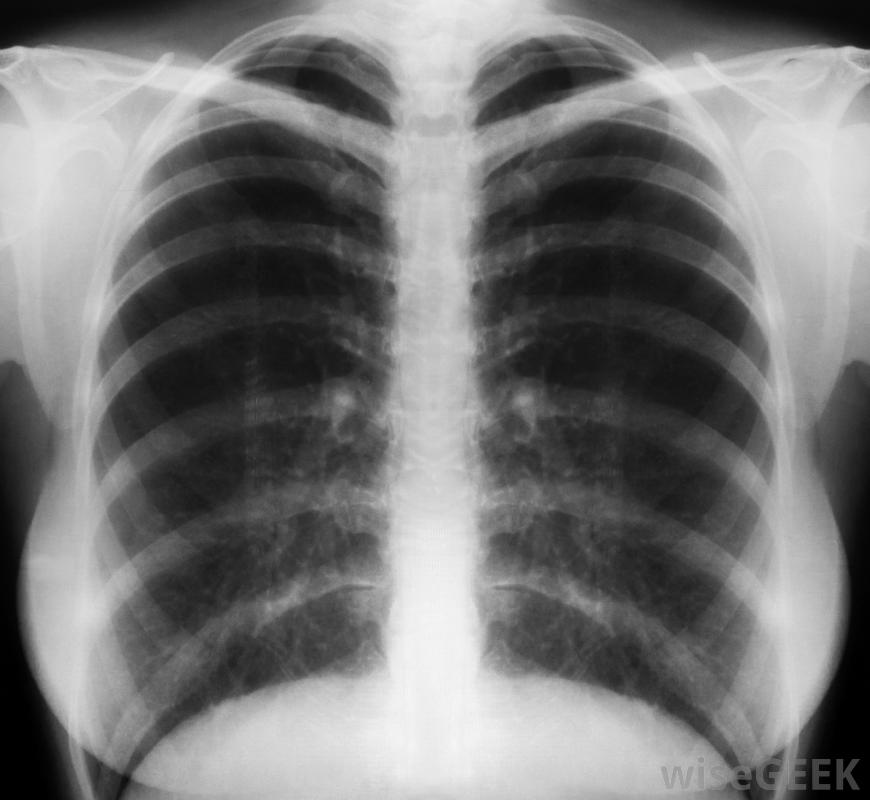

結核病皮膚試驗結果陽性并不一定表明某人患有活動性肺結核或具有傳染性。通常,當一個人回來時,其皮膚試驗呈陽性,需要額外的檢查來確定是否存在活動性肺結核。額外的檢查將包括胸部X光片和對他或她的癥狀的回顧。根據這些結果,可能需要進一步的檢查和治療。胸部x光片可幫助診斷肺結核了解肺結核(TB)皮膚測試結果呈陽性后會發生什么,了解什么是結核病測試非常重要。在PPD測試中,也稱為mantoux測試,在皮膚下注射少量結核病抗原-結核菌素。注射后48到72小時檢查注射部位,檢查皮膚有無隆起區域,稱為硬結。如果結核病皮膚試驗呈陽性,這意味著病人對引起肺結核的細菌有反應,但并不一定意味著病人有癥狀或活動性疾病。需要進一步的診斷在肺結核皮試呈陽性后。如果肺結核皮試結果呈陽性,則第一次檢查通常是胸部X光片。X光片可以確定肺部是否有浸潤或病變,這可能指示活動TB通常也會檢查癥狀清單,以確定是否有結核病的癥狀,如體重減輕、咳血、發燒和盜汗。如果胸部X光檢查正常,沒有癥狀,通常不需要進一步檢查肺結核患者沒有資格獻血。在某些情況下,沒有活動性肺結核但檢測結果呈陽性的人,可能會服用藥物。導致結核病的細菌會出現在皮膚測試呈陽性的人身上,但也可能處于休眠狀態,為了預防這種細菌在將來變得活躍,可以使用藥物預防結核病。結核病是一種傳染性疾病,可能會導致淋巴結腫大當胸部X光片顯示有肺結核的跡象或出現癥狀時,一個人可能患有活動性肺結核,需要分析痰液樣本以確認細菌的存在。病人也需要遠離與其他人的密切接觸,以防止疾病傳播。如果有活動性肺結核,將給予抗生素藥物治療一旦一個人的肺結核皮膚測試呈陽性,他將來很可能會有陽性測試PPD皮膚測試是某些類型就業和入學的常規要求。對于有PPD皮膚測試陽性史的人,通常每年進行一次癥狀檢查表。活躍肺結核將用口服抗生素治療一個療程。